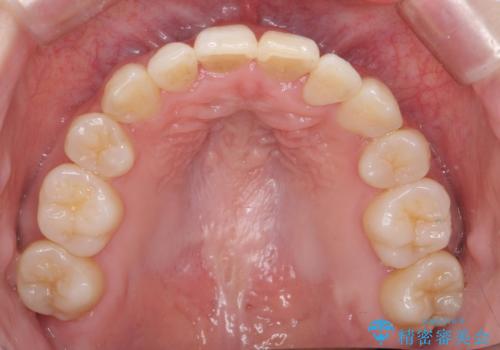

前歯は重度のがたつき、また奥歯はすれ違っていました。

上下左右4本抜歯の可能性を説明していましたが、実際は上顎2本の小臼歯抜歯で済みました。

上下の顎の幅もあっておらず、成人でしたが手術なしで上あごを骨から広げる処置(急速拡大装置)を行いました。